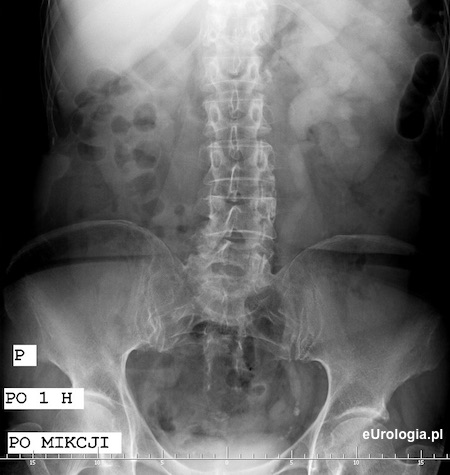

Złóg w dolnym odcinku moczowodu.